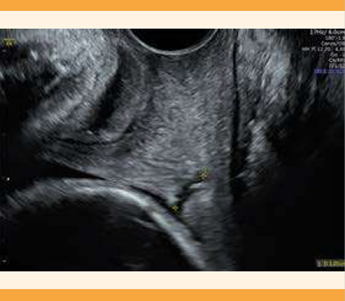

La paciente reingresó a Urgencias a las 27 semanas y 5 días, con actividad uterina y cambios cervicales francos, con reporte de cervicometría de 10 mm que acorta hasta 6 mm al asociarse con la dinámica uterina (Figura 1), escenario clínico en el que se consideró que la paciente no era apta para intervención mecánica (pesario) por lo que luego de descartar una infección subyacente, se procedió a las maniobras propias del parto pretérmino. Se inició el esquema de maduración fetal (una dosis de 12 mg de betametasona cada 24 horas, por vía intramuscular, repetida al siguiente día), neuroprotección con sulfato de magnesio (infusión de 2 g por hora por vía intravenosa) y útero-inhibición con 10 mg de nifedipino cada 20 minutos (tres dosis por vía oral, seguidas de 10 mg cada 6 horas durante 48 horas). Con ese esquema se consiguió la estabilización temporal de la paciente, con posterior atención intrahospitalaria durante el resto del embarazo, ante el riesgo de parto pretérmino. Por último, ante la agudización clínica del cuadro clínico previo, se decidió el inicio de la cesárea, que trascurrió sin complicaciones, por trabajo de parto activo a las 28 semanas y 4 días. Se obtuvo el recién nacido 1, de sexo masculino y 1050 g, cefálico con Apgar de 7 al minuto. Enseguida el recién nacido 2, de sexo masculino y 1065 g, cefálico, con Apgar de 7 al minuto. Por último, el recién nacido 3, de sexo masculino y 1010 g, podálico con Apgar de 6 al minuto.

Figura 1 Cavidad uterina que alberga el embarazo (cervicometría a las 27 semanas y 4 días). Al lado se evidencia el cuello de la cavidad uterina vacía.